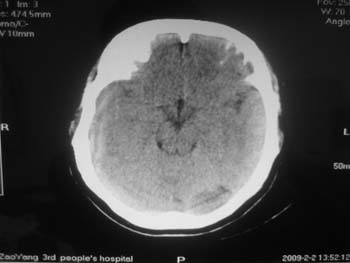

女。44岁,语言障碍三天,右侧上肢时而麻木。时而好转。其它图像未见异常。图像有点差请大家见谅。mg]/upload/forum/2009/02/0214453656449.jpg[/img]

蛛网膜囊肿

双侧额叶密度低,考虑线束老化或脑梗塞?

左侧枕叶脑软化灶?

双侧额叶脑梗塞,左侧枕叶脑软化灶,

临近脑沟五增宽,考虑蛛网膜囊肿